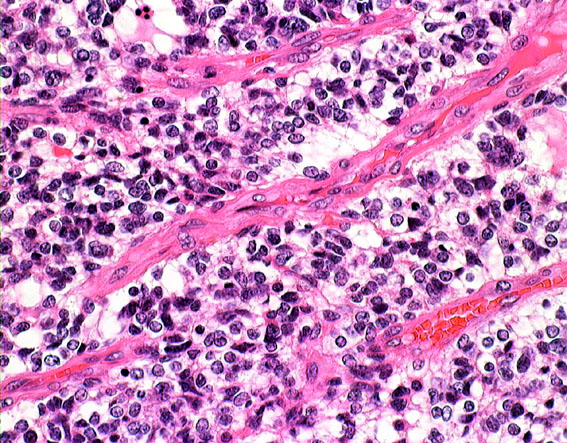

HE染色では細胞核の周りが抜けるような典型的なhalo(左側の写真)があります。1p/19q欠失があり,MIB染色率(右側)は4%でした。

一部で,細胞密度が高く,核の腫大とクロマチンの増量,核間距離の短縮があり,核分裂像が認められ,MIB-1染色率が10%です。組織学的には退形成性乏突起膠腫グレード3とされました。

IDH変異あり,1P/19q欠失あり,ATRX変異なしです。

部分像だけでは星細胞系腫瘍と見分けはつかない

この部分のみを一見するとanaplastic astrocytomaです。しかし,他の大部分がoligoastrocytomaであり,かつての組織診断ではanaplastic oligoastrocytoma AOA WHO grade IIIです。

左側の病理像はanaplastic oligodendroglioma AO あるいはoligodendroglioma ODです。しかし,右の画像の様にpseudopallisading (necrosis)を示す部分があり,WHO grade 4と診断したくなるのですが,oligodendrglioma grade 3 ではnecrosisが混在してもgrade 3としてよいのです。